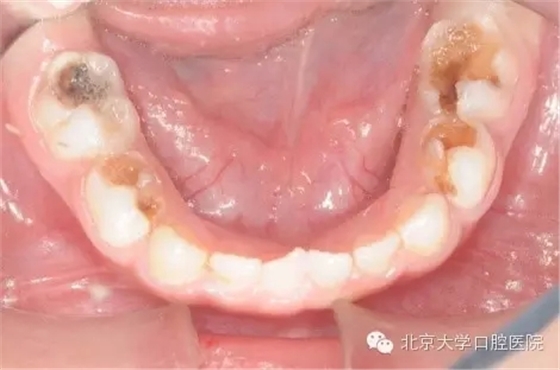

全身麻醉下兒童牙齒治療是一項(xiàng)針對(duì)在口腔醫(yī)學(xué)臨床工作中難于對(duì)牙科恐懼癥患兒、低齡及智障兒童實(shí)施常規(guī)口腔診療的特色技術(shù)項(xiàng)目。從1999年開(kāi)始,北京大學(xué)口腔醫(yī)院兒童口腔科和麻醉科相互協(xié)作在國(guó)內(nèi)率先開(kāi)展該治療技術(shù)。近二十年來(lái),北大口腔醫(yī)院兒科已建成了設(shè)備先進(jìn)的全麻治療室,累計(jì)完成全麻下牙齒治療患者數(shù)千例,使該技術(shù)成為北大口腔醫(yī)院特色醫(yī)療技術(shù)之一。該治療技術(shù)優(yōu)點(diǎn)是在一次治療中醫(yī)生可以高質(zhì)高效地完成全口所有需進(jìn)行的治療工作,特別適用于配合能力差,治療需要量大的患兒。

全身麻醉下的牙齒治療是對(duì)已經(jīng)出現(xiàn)齲壞,牙髓根尖病變的牙齒進(jìn)行治療,是“亡羊補(bǔ)牢”治療本身并沒(méi)有預(yù)防再患齲的作用,而培養(yǎng)孩子良好的口腔衛(wèi)生習(xí)慣才能起到防患于未然的作用,這需要家長(zhǎng)在日常生活中與孩子一起努力。